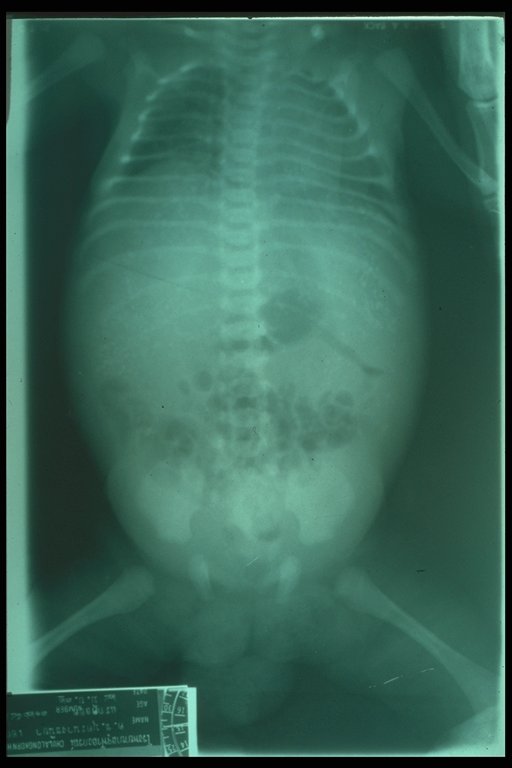

Meconium peritonitis. A classical abdominal X-ray demonstrates calcified extravasated meconium in the peritoneal cavity since fetal growth. Free air in the abdomen (football sign) is also noted.